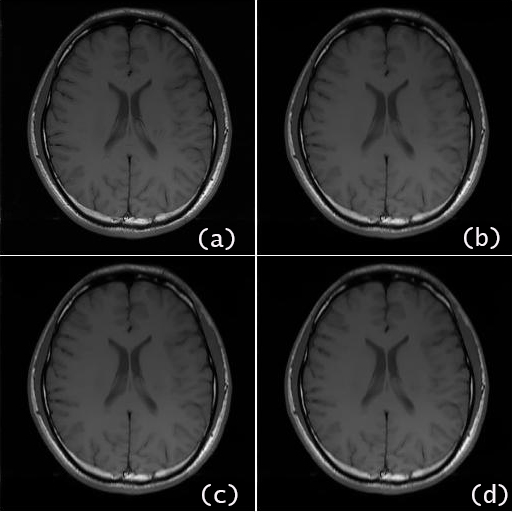

For the brain data set, the reconstructed images by the proposed algorithm using undersampled -space data of nominal reduction factor, and higher and are shown in Fig.2 (b), (c) and (d), respectively, in comparison with the SOS image using the full space data in Fig.2 (a). For the brain date set of , Fig.3 presents the reconstructed image by the proposed method in comparison with that by other recent algorithms, which are IRGN-TGV [7], SPIRiT [4] and Sparse-BLIP [8]. To provide more detailed reconstruction information for comparison, a selected area of each reconstructed image by different algorithms is zoomed and displayed in Fig. 4.